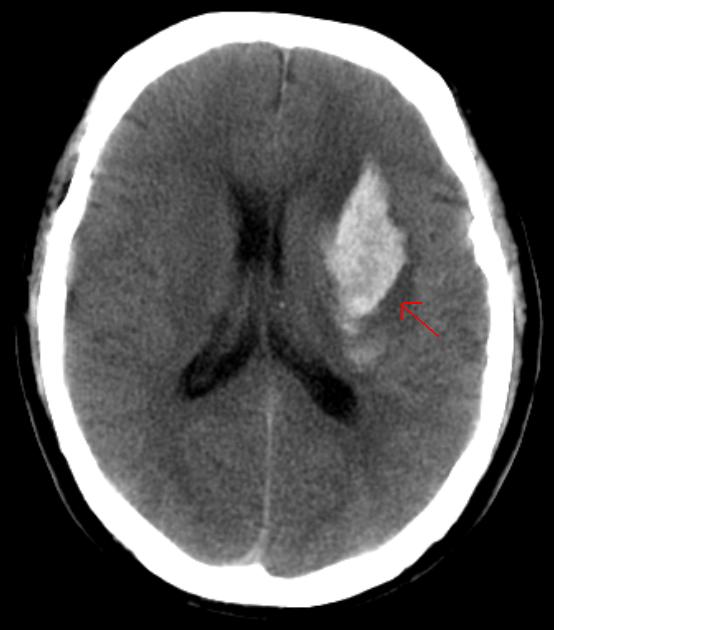

因局部血管破裂导致血液外溢,侵入脑组织所引起的卒中称为出血性卒中